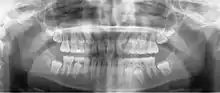

A panoramic radiograph is a panoramic scanning dental X-ray of the upper and lower jaw. It shows a two-dimensional view of a half-circle from ear to ear. Panoramic radiography is a form of focal plane tomography; thus, images of multiple planes are taken to make up the composite panoramic image, where the maxilla and mandible are in the focal trough and the structures that are superficial and deep to the trough are blurred.

![]() A dental panoramic radiograph, showing the maxilla and mandible, all the teeth including the "wisdom teeth," the frontal and maxillary sinuses, the nasal cavity and the temporomandibular joint and other near by head and neck anatomy. | |